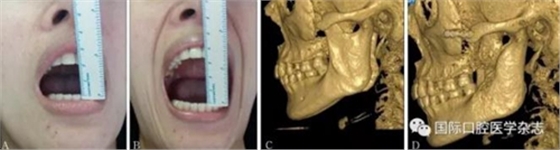

A:術(shù)前開口度;B:術(shù)后開口度;C:術(shù)前影像學(xué)檢查片;D:術(shù)后影像學(xué)檢查片。

圖 18 關(guān)節(jié)盤復(fù)位錨固術(shù)前后對(duì)比